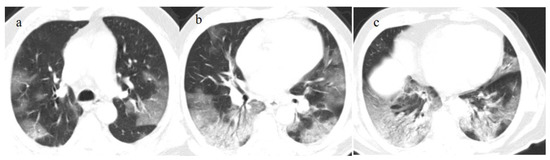

- Melhorn, J.; Achaiah, A.; Conway, F.M.; Thompson, E.M.; Skyllberg, E.W.; Durrant, J.; Hasan, N.A.; Madani, Y.; Naran, P.; Vijayakumar, B.; et al. Pneumomediastinum in COVID-19: A phenotype of severe COVID-19 pneumonitis? The results of the United Kingdom (POETIC) survey. Eur. Respir. J. 2022, 60, 2102522. [Google Scholar] [CrossRef]

- Khaire, N.; Deshmukh, S.; Agarwal, E.; Mahale, N.; Khaladkar, S.; Desai, S.; Kulkarni, A. “Pneumomediastinum: A marker of severity in COVID-19 disease”. Heliyon 2023, 9, e12981. [Google Scholar] [CrossRef] [PubMed]

- Tetaj, N.; Garotto, G.; Albarello, F.; Mastrobattista, A.; Maritti, M.; Stazi, G.V.; Marini, M.C.; Caravella, I.; Macchione, M.; De Angelis, G.; et al. Incidence of Pneumothorax and Pneumomediastinum in 497 COVID-19 Patients with Moderate–Severe ARDS over a Year of the Pandemic: An Observational Study in an Italian Third Level COVID-19 Hospital. J. Clin. Med. 2021, 10, 5608. [Google Scholar] [CrossRef] [PubMed]

- Kecskes, G.; Szabo, A.; Sutori, D.; Maroti, P.; Marovics, G.; Molnar, T.F. Pneumothorax/pneumomediastinum and pre-existing lung pathology in ventilated COVID-19 patients: A cohort study. J. Thorac. Dis. 2022, 14, 4733–4740. [Google Scholar] [CrossRef] [PubMed]

- Coppola, M.G.; Lugarà, M.; Tamburrini, S.; Madonna, P.; Panico, C.; Noschese, G.; Pone, E. Pneumomediastinum and Pneumothorax as Relevant Complications of Sub-Intensive Care of Patients with COVID-19: Description of a Case Series. Medicina 2021, 57, 919. [Google Scholar] [CrossRef]

- Palumbo, D.; Campochiaro, C.; Belletti, A.; Marinosci, A.; Dagna, L.; Zangrillo, A.; De Cobelli, F. Pneumothorax/pneumomediastinum in non-intubated COVID-19 patients: Differences between first and second Italian pandemic wave. Eur. J. Intern. Med. 2021, 88, 144–146. [Google Scholar] [CrossRef]